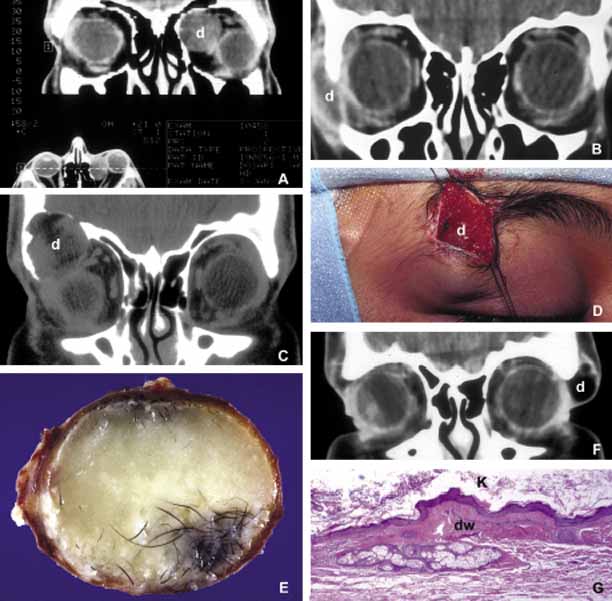

Most of the dermoids are well outlined by ultrasonography because of their anterior location thus making CT or MRI rarely necessary.19 If the dermoid is unusually large or located at the frontal zygomatic suture, CT is necessary to document the relationship of the lesion to the bone before surgical intervention. Rarely, dermoids at the fronto-zygomatic suture may develop dumbbell-shaped lesions partially within the orbit and partially extending into the temporal fossa.20,21 Unusually large superior orbital dermoids particularly those that leak and create granulomatous reaction within adjacent soft tissues may erode the bone and extend into the frontal sinus or the cranium (Fig. 2).

Fig. 2 Dermoid. Different presentations of dermoid (d): superior medial, semi-solid mass pushing the globe down and out (A); a ruptured dermoid causing an inflammatory reaction within adjacent soft tissues (B); a large superior lateral dermoid eroding through the roof of the orbit to extend into the brain (C); extraorbital dermoid within the subcutaneous tissues of the eyebrow (D); gross appearance of the cystic dermoid containing whitish yellow cheesy keratin material intermixed with hair (E); dumbbell dermoid that is present on both sides of the frontozygomatic fissure (F); histopathology of dermoid wall (dw) containing skin appendages, the lumen of the dermoid is lined with stratified squamous epithelium producing keratin (K) (G). ([E] is the courtesy of Amin M. Nasr, MD of Beirut, Lebanon)